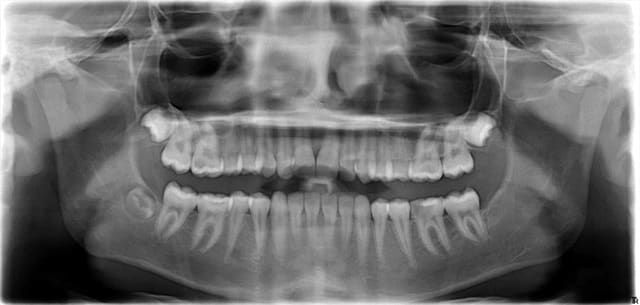

Voilà la panoramique, vous constaterez que

1°) il n'y a pas de 38

2°) pour une gamine de 13 ans, la denture est plutôt avancée, d'où pour moi la difficulté de mésialer la 37 correctement.

Les 16-26-46 ont été traitées avec soin conservateur.

J'espère bien être là dans 5 ans pour voir le résultat, si la patiente est encore dans les parages.